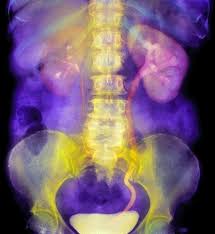

Kidney Stone Ultrasound Break Up. The doctor uses an x ray or ultrasound to find the stone or stones in your kidney. Yes doctors are starting to use ultrasound called lithotripsy to break up kidney stones rather than resorting to surgery if they can t be passed.

Specific ultrasound imaging mode optimized to visualize kidney. Works by focusing high energy shock waves to break up kidney stones. A noninvasive procedure that uses shock waves to break up the kidney stone into.

Then they aim high energy shock waves at your kidney from the outside. Percutaneous nephrolithotomy pnl is a type of surgery to break apart and. The kidneys are located in the abdomen in the retroperitoneal area. Most techniques involve inserting a disintegrating device through the bladder to break up the blockage.